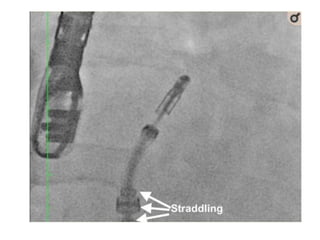

• The Clip Delivery System (CDS) is advanced

until its tip is even with the guide tip under

fluoroscopic guidance.

• The CDS is further advanced until the guide

radiopaque tip ring marker is centred between

the sleeve alignment markers with

confirmation on fluoroscopy (straddling)

• Steering andpositioning of the MitraClip delivery system in the LA. • The Clip Delivery System (CDS) is advanced until its tip is even with the guide tip under fluoroscopic guidance. • The CDS is further advanced until the guide radiopaque tip ring marker is centred between the sleeve alignment markers with confirmation on fluoroscopy (straddling)

• #25 Steering and positioning of the MitraClip delivery system in the left atrium. The Clip Delivery System (CDS) is advanced until its tip is even with the guide tip under fluoroscopic guidance. The CDS is further advanced until the guide radiopaque tip ring marker is centred between the sleeve alignment markers with confirmation on fluoroscopy (straddling)